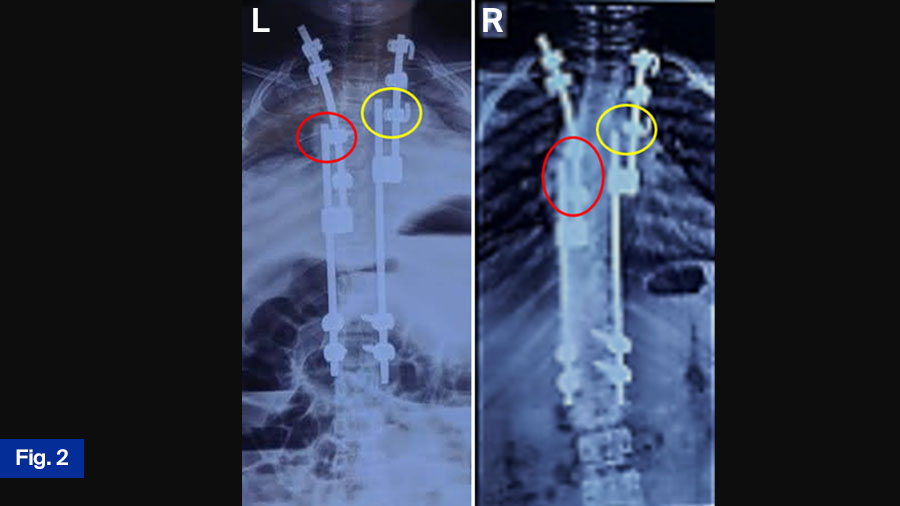

APC is a hybrid of guided growth and apex control through non fusion and reversed modulation-based philosophies for management of growing-spine deformity. It replaces the apical fusion of a traditional SHILLA with procedures (compression/distraction + medial translation + derotation) against primary drivers of curve progression, as shown in Figure 1, Figure 2.

- Using dominos with a hole equal to the rod diameter to overcome soft tissue impinging preventing rod sliding, shown in Figure 2.